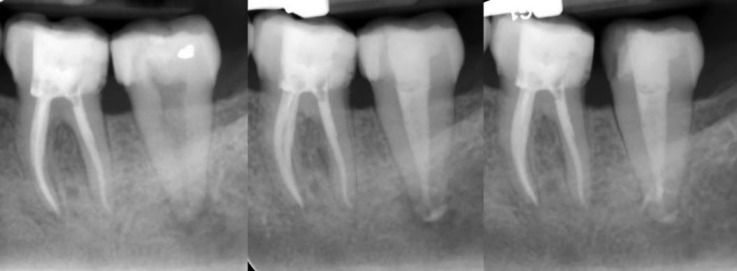

Bio-obturation is an innovative approach in root canal therapy that effectively addresses complex clinical challenges using bioactive endodontic materials. This report highlights 14 diverse cases where bio-obturation was employed to manage complications such as internal and external resorption, root perforations, draining sinus tracts, mechanical obstructions, and trauma-related injuries. The outcomes demonstrate notable healing and resolution of various tooth related pathologies in failed primary root canal treatments. Root perforations and canal blockages were successfully sealed, restoring the integrity of the root canal system and ensuring continued tooth function and retention. Bio-obturation facilitated stabilization and regeneration of periradicular and supporting tissues in trauma cases, including avulsed teeth and inflammatory root resorption. Cases involving open apices, dens invaginatus, and complex root canal anatomy also showed favorable results. Overall, bio-obturation offers a transformative alternative to conventional root canal filling by promoting enhanced biological sealing and improved periradicular healing, thus increasing the probability of sustainable long-term clinical success. While calcium-enriched mixture cement served as the bioactive material in these cases, this approach may also be effectively implemented using other advanced calcium silicate-based biomaterials, broadening its applicability in challenging endodontic scenarios.